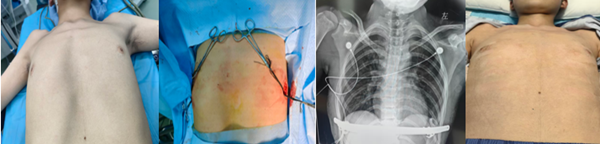

近日,蚌埠醫(yī)科大學(xué)第一附屬醫(yī)院胸外科團(tuán)隊(duì)成功為一名 14 歲的復(fù)雜胸壁畸形患者實(shí)施 “三明治” 聯(lián)合矯形術(shù),標(biāo)志著蚌埠醫(yī)科大學(xué)第一附屬醫(yī)院在胸壁畸形矯形領(lǐng)域邁入新高度,為更多復(fù)雜病例的治療提供了關(guān)鍵解決方案。

手術(shù)過程中,王偉醫(yī)生帶領(lǐng)團(tuán)隊(duì)精準(zhǔn)操作,采用 “三明治” 聯(lián)合矯形法:在患者胸腔內(nèi)放置 NUSS 鋼板以支撐凹陷胸壁,同時(shí)在胸廓外皮下固定另一塊鋼板,通過內(nèi)外雙重固定的方式,精準(zhǔn)矯正胸壁的不對(duì)稱畸形。

術(shù)后復(fù)查顯示,小史的胸廓形態(tài)得到顯著改善,原本隆起、凹陷的胸壁恢復(fù)平整,駝背與脊柱側(cè)彎問題也得到有效緩解。更讓家人欣慰的是,小史的精神狀態(tài)明顯好轉(zhuǎn),臉上重新露出笑容,對(duì)回歸校園、參與集體活動(dòng)充滿了期待。